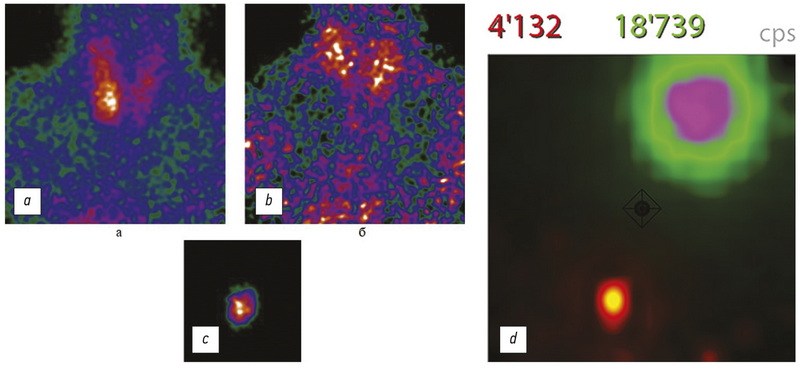

Methods of medical visualization and thermal ablation as a new approach to treatment of hyperparathyroidism

The pathologies of parathyroid glands are widespread among endocrine system diseases, excluding diabetes and thyroid pathology. There are only two methods that are used to treat hyperparathyroidisms, such as surgery and conservative therapy. However, transracial thermal destruction methods (ablation) have recently appeared in clinical practice. The methods have good precision and connect with physical phenomena, such as interaction laser, radiofrequency, microwave, and HIFU irradiation with bio substance. The review is dedicated to critically analyze the modern methods for local thermal destruction of the hyper-functioning parathyroid glands. The review includes data from randomized clinical trials from 2012 to 2021. The studies were from Google Scholar and Pubmed with a total number of 1,938 patients (laser ablation ― 216 patients, radiofrequency ablation ― 225, microwave ablation ― 1467, high-density ultrasound ablation ― 30 patients). Recommendations methods of thermal destruction application were obtained during the review. Furthermore, we have designed some algorithms for hyperparathyroidism treatment. Moreover, thermal destruction methods were observed. There are four modern methods of thermal destruction which have been analyzed like alternatives to surgery. Each of them has advantages and disadvantages, its profile of safety and effectiveness. After processing information from a proven database, the most popular among specialists is methods of microwave ablation. However, laser ablation is more effective than other ways.

Radiotheranostics is here to help

The COVID-19 pandemic did not diminish interest in radiotheranostics. However, the demand for visualization of pathological processes using cross-sectional and hybrid imaging (CT, MRI, SPECT, and PET) is increased. Over the past 15 months, the world has seen an exponential increase in investment in new radiopharmaceuticals for radiotheranostics. The list of antibodies and ligands labeled with "medical" radioactive isotopes is expanding as the molecular mechanisms of regulation and implementation of metabolic processes become clearer. The range of diagnostic and therapeutic radioactive isotopes is also expanding, ultimately increasing the range and availability of radiotherapy in nuclear medicine centers worldwide. It is necessary to unite the efforts of physicists, radiopharmacists, chemists, biologists, doctors, and mathematicians to develop radio technology. Usage and improvement of personalized dosimetry for planning radionuclide therapy is also a priority. For example, the International Foundation Oncidium helps with information and exchange of experience, while the international diagnostic study NOBLE increases the availability and reduces the cost of PSMA receptor scintigraphy. An association for the development of theranostics was created to intensify the integration renewal of nuclear medicine.